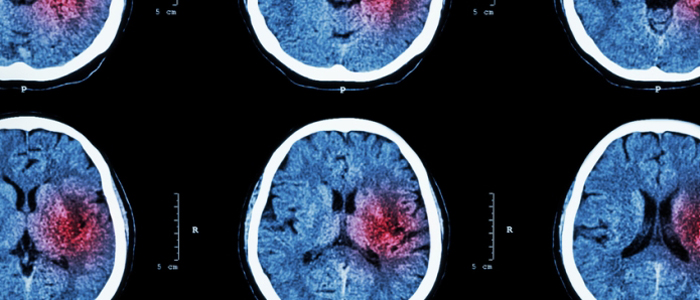

Dialysis patients at risk of progressive brain injury

Mon, 10 Dec 2018 00:05:00 GMT

UofG scientists awarded major grant to better understand brain bleeding

Tue, 30 Jan 2018 10:16:00 GMT